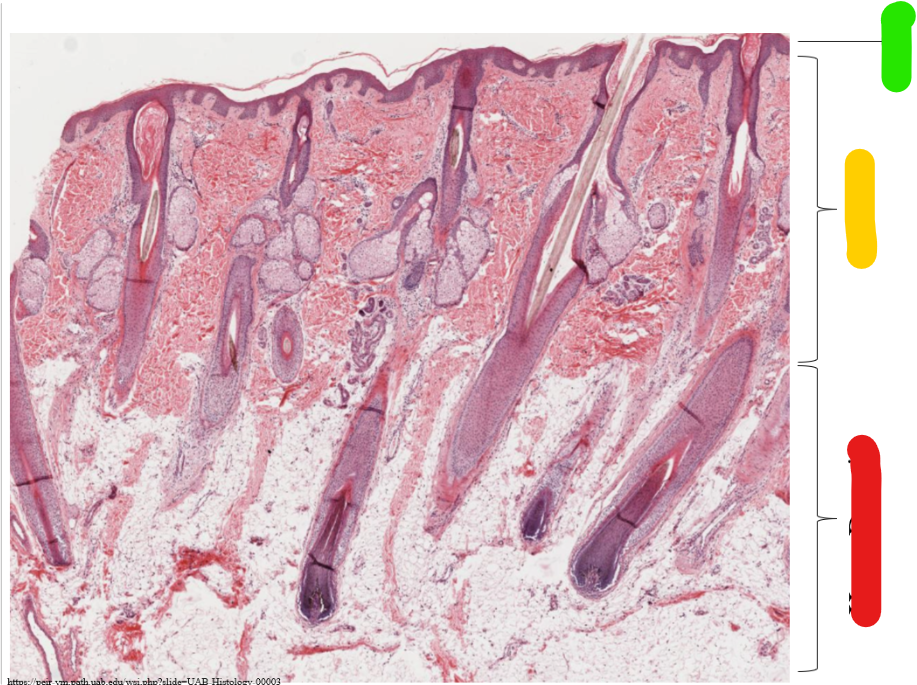

thick skin

green

epidermis

yellow

dermis

red

hypo dermis